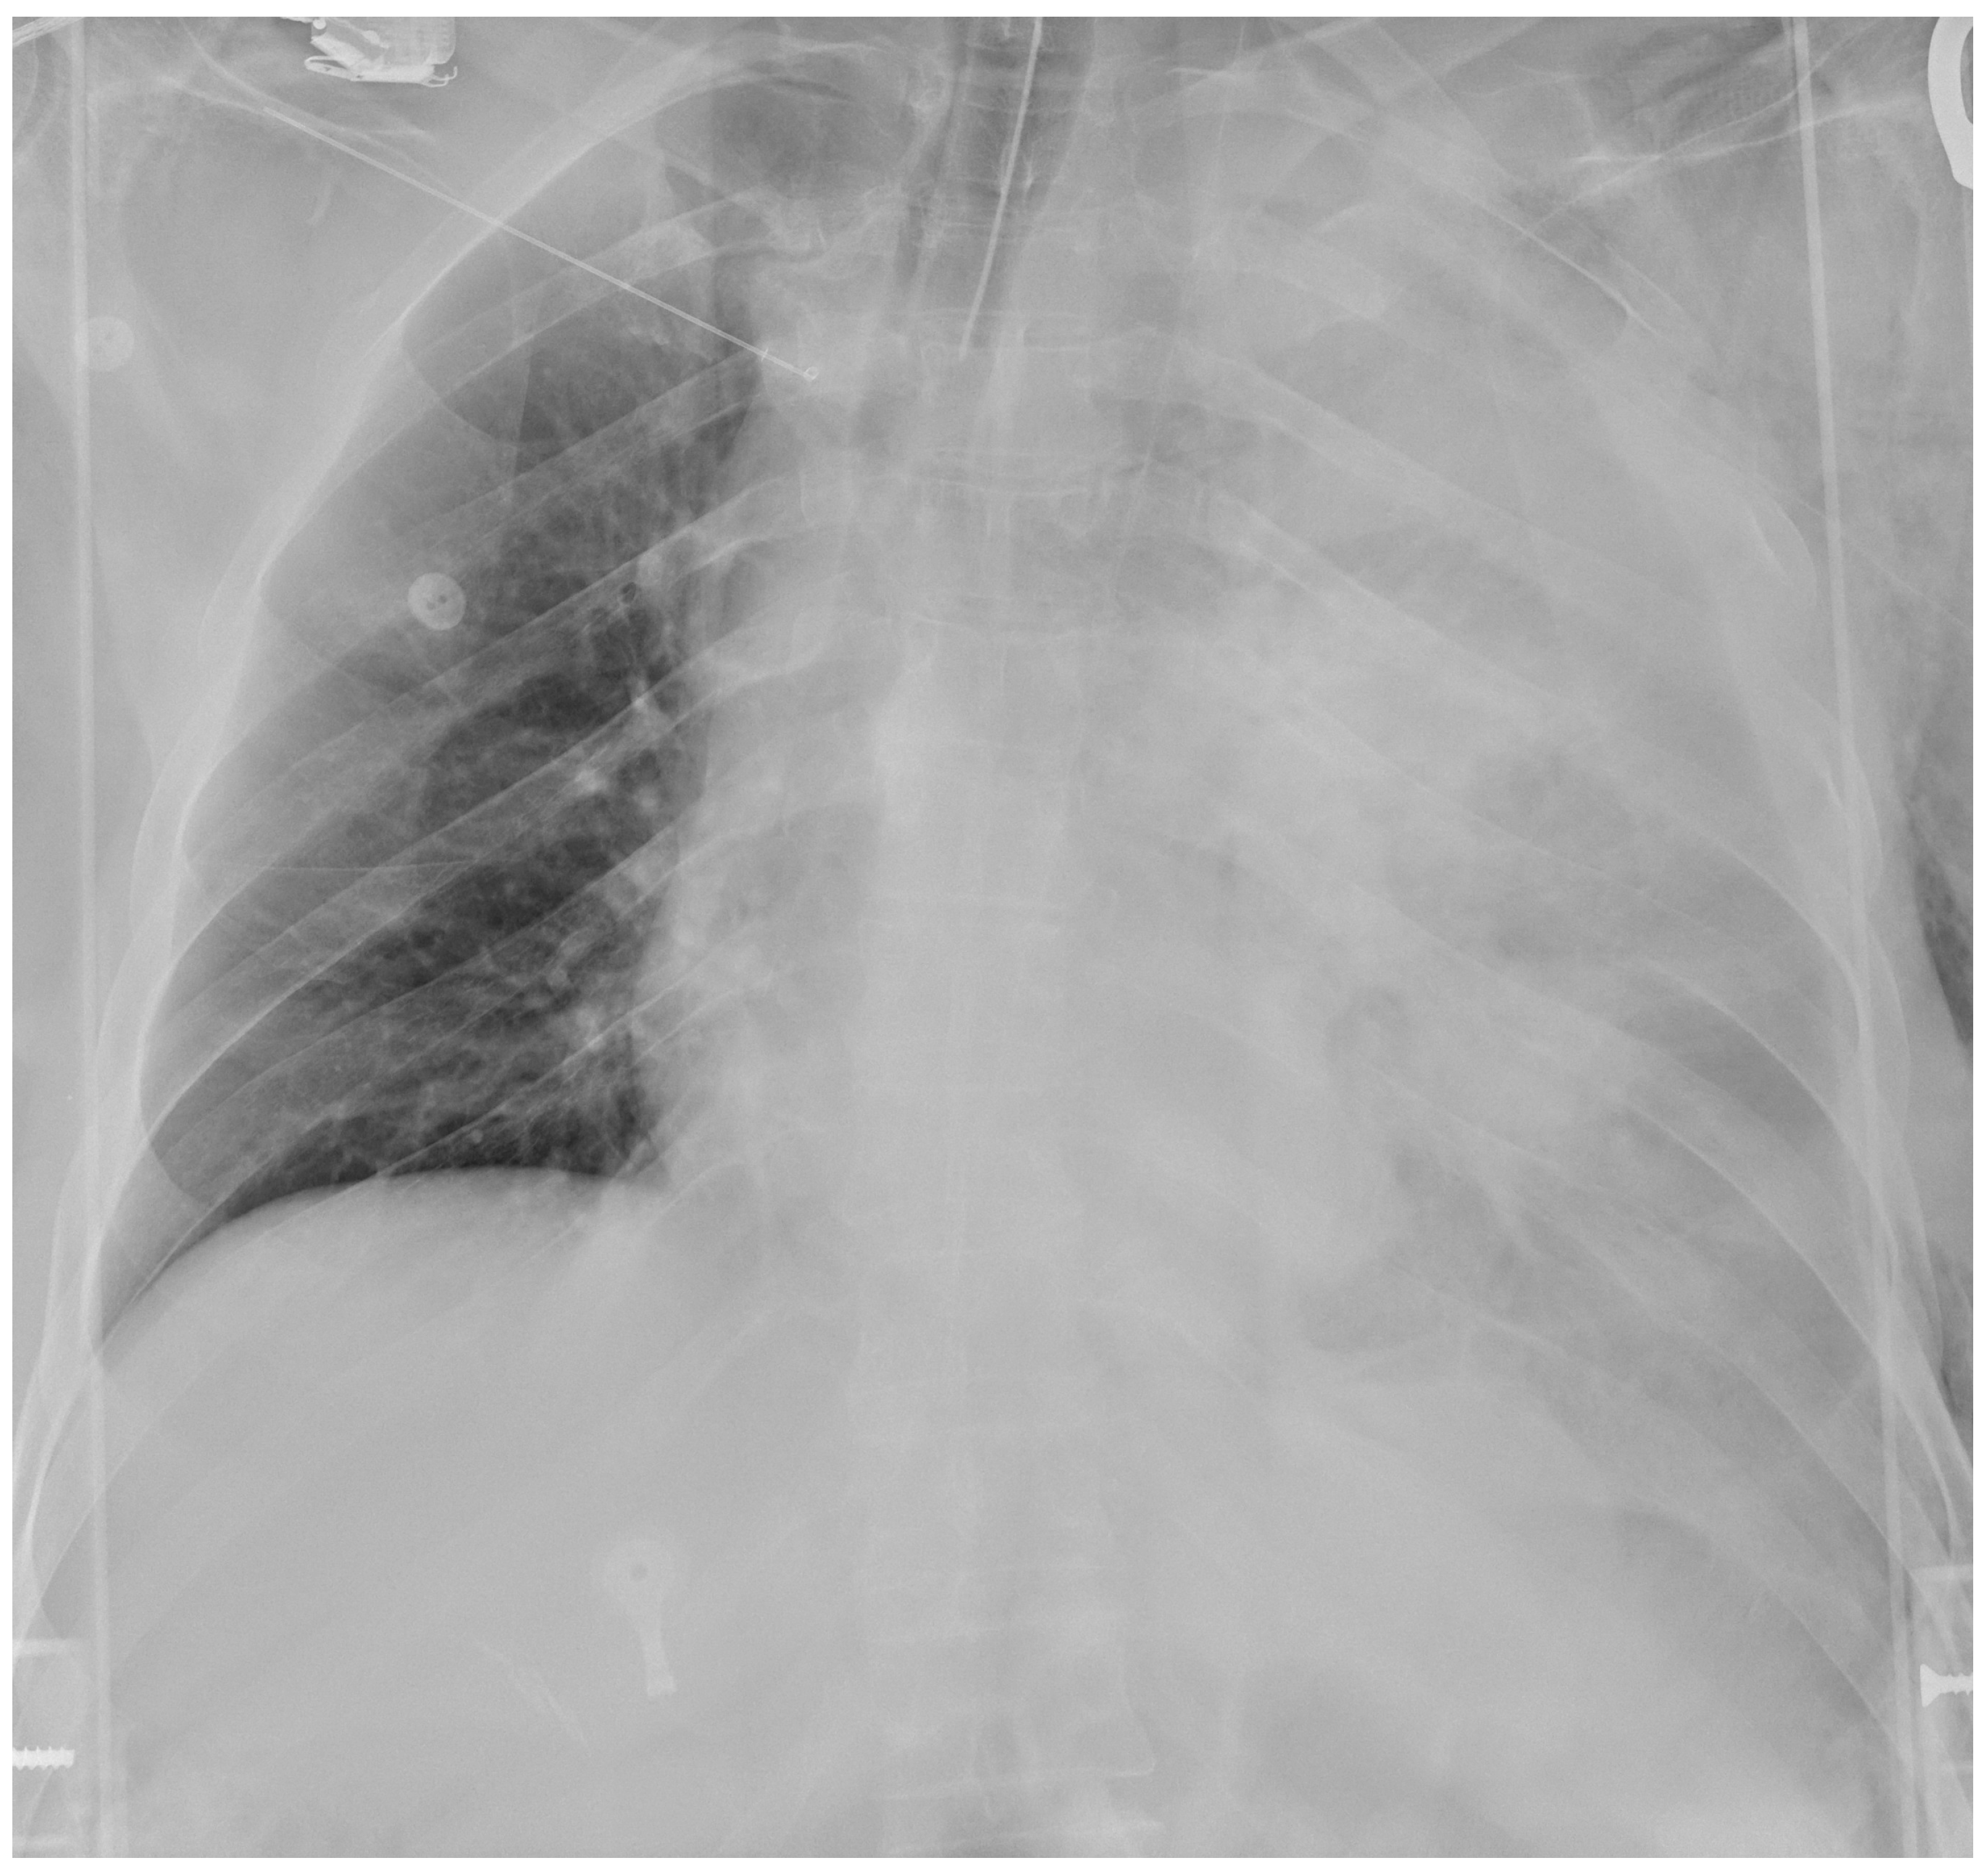

A 53-year-old man with a self-inflicted gunshot wound to the chest was admitted to our Emergency Department. He was hemodynamically unstable, with low values of blood pressure (70/40 mmHg), tachycardia (120 beats per minute) and hypoxemia (peripheral oxygen saturation 80%). Medical examination revealed a 12 mm, round, bullet entry wound at the 3rd intercostal space on the left midclavicular line. An emergency bedside ultrasonography (Point of Care Ultrasound—POCUS) revealed left pleural and pericardial effusion. He was intubated, transfused with one blood bag of iso rhesus, and ev fluid instillation and vasoconstrictor support were started. A chest film showed massive left-sided pleural effusion (Figure 1). Blood samples were as following: hemoglobin concentration 10.6 g/dL, Platelet count 176,000/mmc, Prothrombin Time (PT) 53%, Partial Thromboplastin Time (PTT) 27 s, INR 1.42. His past medical history was characterized by systemic hypertension, treated with Calcium Antagonist 10 mg/die and Acetylcholinesterase inhibitor 10 mg/die. Due to unresponsive hemodynamic instability, the patient was immediately transferred to the operating room by the cardiac and thoracic surgery teams without any further instrumental examination.

Figure 1. Admission chest film showing massive left hemothorax.